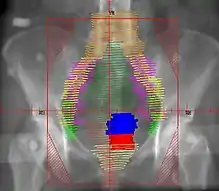

Example of an AP radiation therapy treatment field for Stage IB2+ Cervix used at Tufts/Brown residency program. Actual patient contours should guide field design.